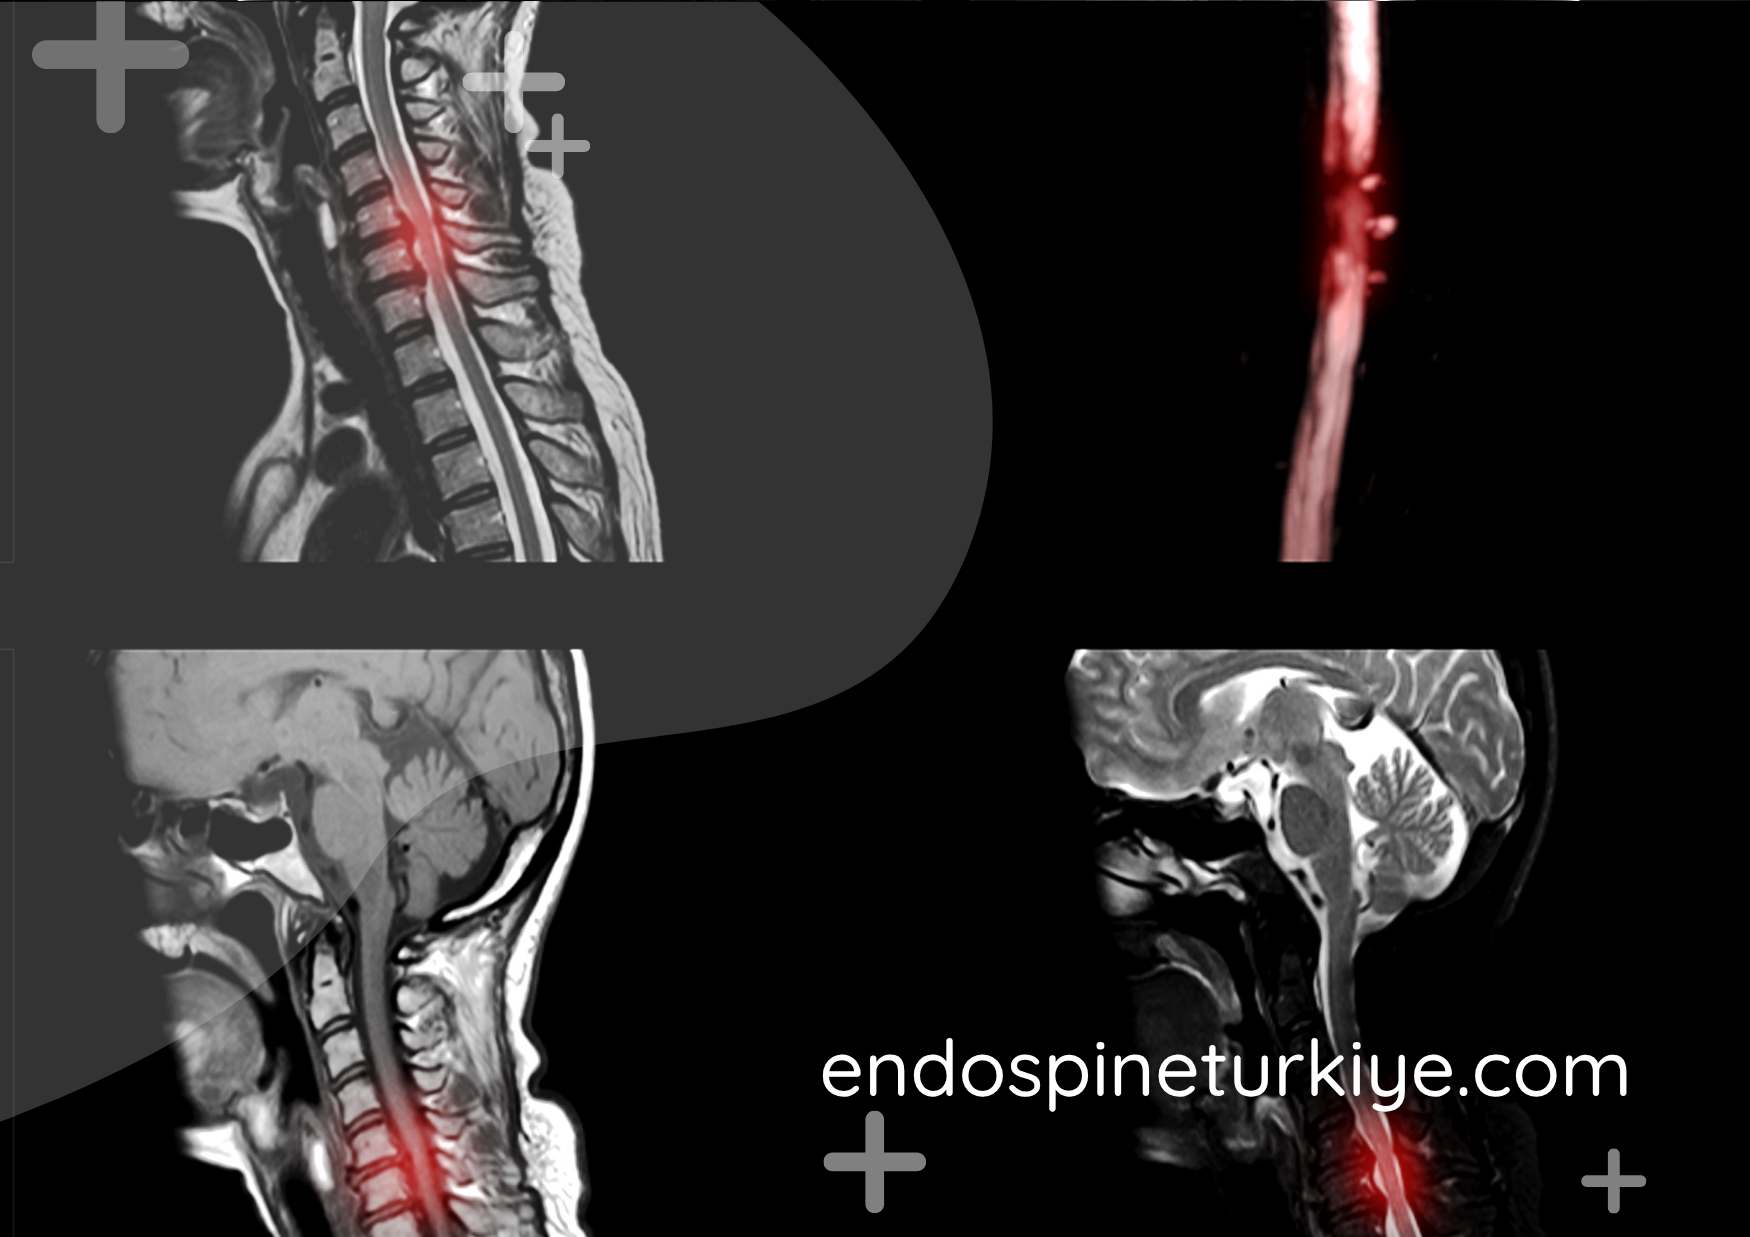

Boyun fıtığı MR görüntüsü - servikal disk hernisi

Boyun fıtığı (servikal disk hernisi) MR görüntüsü